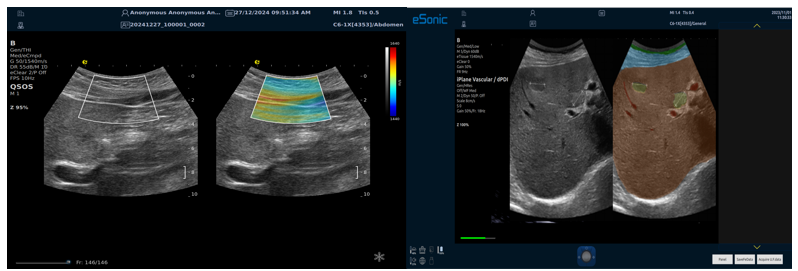

QSOS声速定量成像

测量原理

QSOS声速成像技术利用声波在组织中的传播速度差异性,计算不同位置的声速值,反映组织的物理特性。

成像过程

利用超声探头发射超声波脉冲,分析反射信号的时间延迟,确定声波传播路径和速度,构建声速分布图像。

图像显示

QSOS技术采用彩色编码显示声速图像,不同颜色代表不同声速值,便于医生识别病变部位和测量。

25fb8cb17586b86e5d915a2be3025a2.png

技术优势

?精准定量反映组织特性,成像更敏锐?彩色编码直观显示,轻松发现异常?捕捉声速差异,早期、微小病变更易察觉

肌骨22.png

肌骨领域的应用

?精准定位损伤部位?判断损伤严重程度?监测肌肉营养?评估肌少症?骨质疏松评估